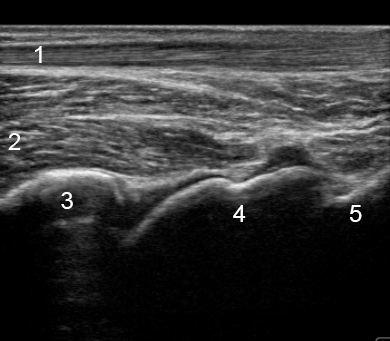

足首後脛骨陥凹

アキレス腱

長母趾屈筋(FHL)

脛骨

距骨

踵骨